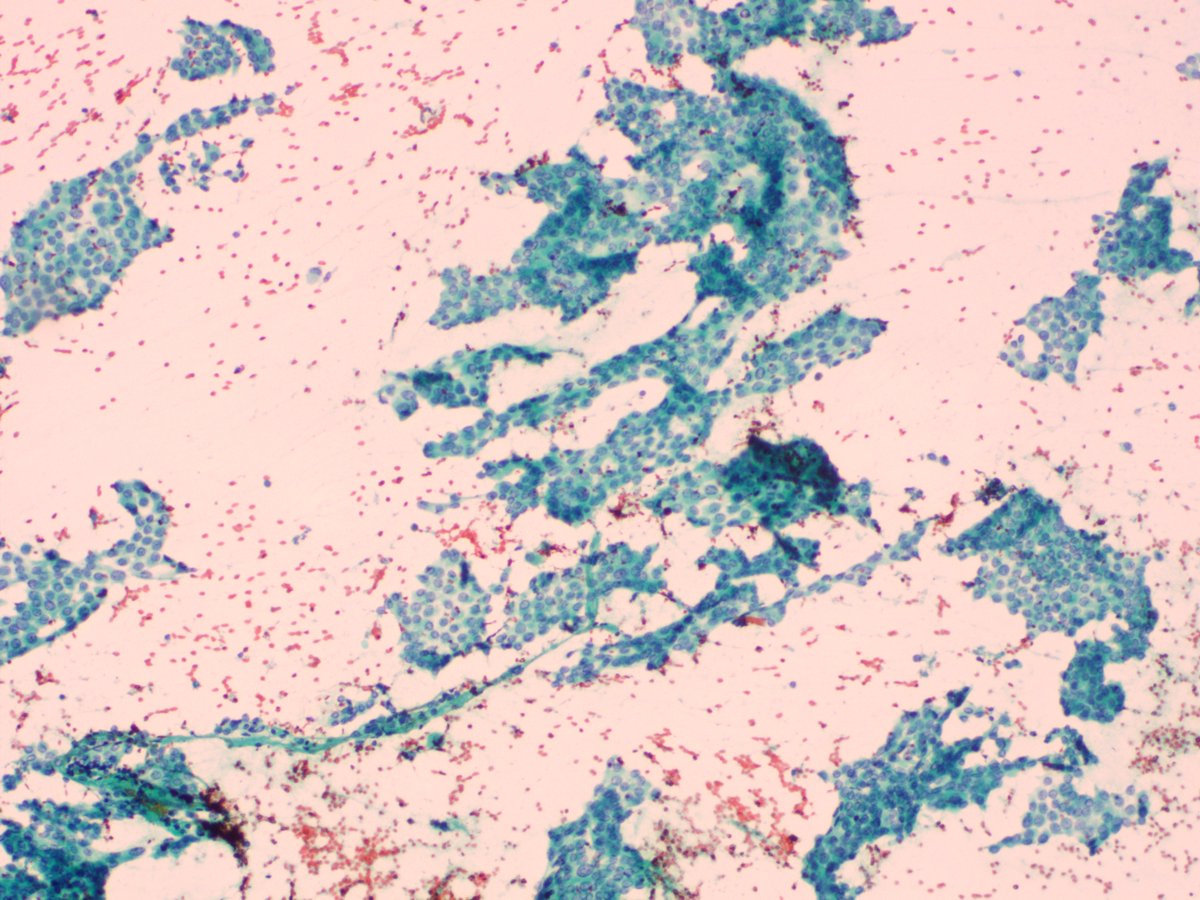

https://t.co/WwKCEU7O2g Rawat G, Aiyer HM, Shukla A, Dharmani S. Acute Invasive Fungal Thyroiditis - A Catastrophic Event Post-Renal Transplant. Indian J Nephrol. 2024;34(5):540-541. #pathtwitter #mucormycosis #headandneckpath

pmc.ncbi.nlm.nih.gov